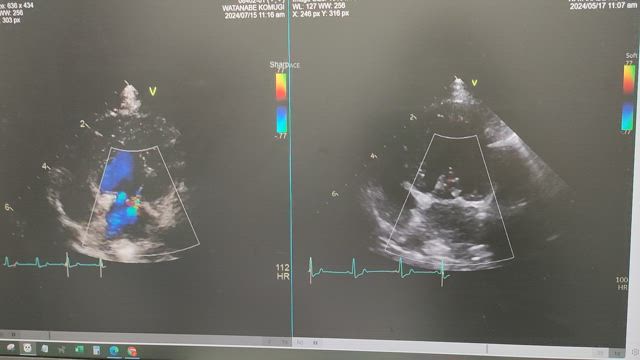

術後3カ月検診